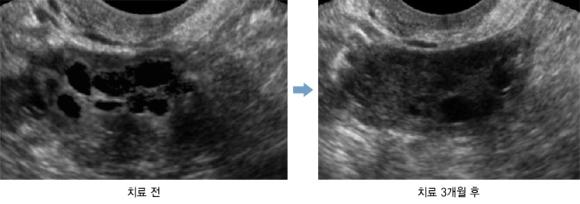

김씨는 3개월 간 한약 복용과 침 치료를 통해 월경 주기가 67일에서 39일로 정상화 감소했다. 또 평소 자주 겪던 소화불량과 어지러움·몸의 붓기가 감소했다. 치료 후 골반 초음파 검사 결과, 배란이 안 된 채 남아있던 우측 난소의 난포 개수가 현저하게 감소했다.